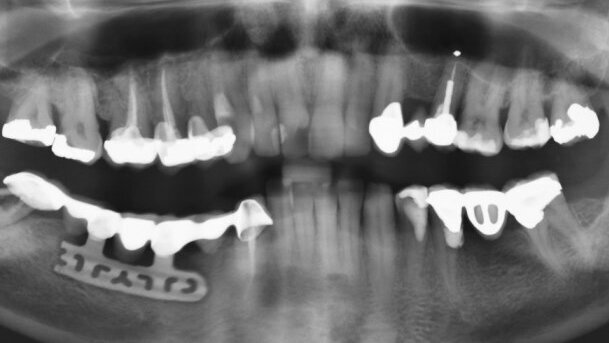

54-letni pacjent, bez chorób ogólnoustrojowych, zgłosił się z powodu ruchomości uzupełnienia protetycznego zębów 43-48. Implant żyletkowy w pozycji 44-46 został wszczepiony 22 lata wcześniej.

W badaniu klinicznym stwierdzono objawy stanu zapalnego tkanek miękkich wokół implantu oraz ruchomość III° zęba filarowego 48. W badaniu radiologicznym uwidoczniono zmiany osteolityczne wokół implantu żyletkowego oraz wokół korzeni zęba 48.

Uzupełnienie protetyczne zostało przecięte. Implant żyletkowy wykazywał III° ruchomości wg Entina, a jego ekstrakcja nie wymagała dodatkowego opracowywania kości. Dokonano również ekstrakcji korzeni zęba 48. Rana poekstrakcyjna została zaopatrzona materiałem Bio-Oss Collagen (100 mg) i zaszyta. Zabieg został wykonany w osłonie antybiotykowej, a antybiotykoterapię stosowano przez 7 dni (Augmentin 2 x 1).

Po 12 miesiącach od usunięcia implantu żyletkowego, w pozycjach 43, 44, 45, 46 zostały wszczepione 4 implanty stożkowe o wymiarach odpowiednio: poz. 43 – 3,5 x 11,5 mm, poz. 44 – 3,5 x 13 mm, poz. 45 – 4,3 x 10 mm, poz. 46 – 4,3 x 11,5 mm. Ostatecznie w pozycji 36 został wszczepiony implant 4,3 x 10 mm. Po kolejnych 5 miesiącach wykonano docelowe uzupełnienia protetyczne. Po 2 latach obserwacji, wynik leczenia jest stabilny. Odbudowa protetyczna pozostaje w pełni funkcjonalna i akceptowalna dla pacjenta.